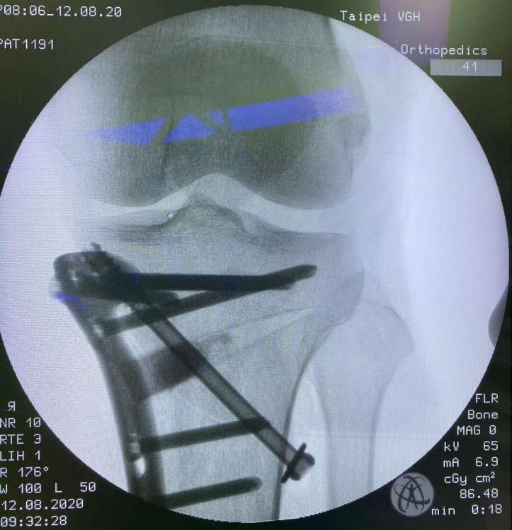

第二阶段治疗:即手术治疗,患者膝关节未达到软骨下骨磨损破坏的程度,则可选择胫骨上段截骨钢板内固定术(HTO)。

第三阶段治疗:如果患者膝关节病变集中在单侧,对侧关节里面软骨全层完整,膝关节内外侧副韧带及前后交叉韧带完好,则可行单髁置换术手术。 第四阶段治疗:膝关节内外侧关节软骨均损伤,比如类风湿性关节炎、强直性关节炎、膝关节的感染导致关节软骨破坏感染控制后等等,则需行全膝关节置换术。 (本图:左侧是截骨矫形内固定术后,右侧是全膝关节置换术后) 膝关节骨性关节炎阶梯治疗的有效路径及模式,可达到疾病有效治疗,保护有效劳动力,减少老年人因病致残生活不便引发的社会及家庭医疗负担。